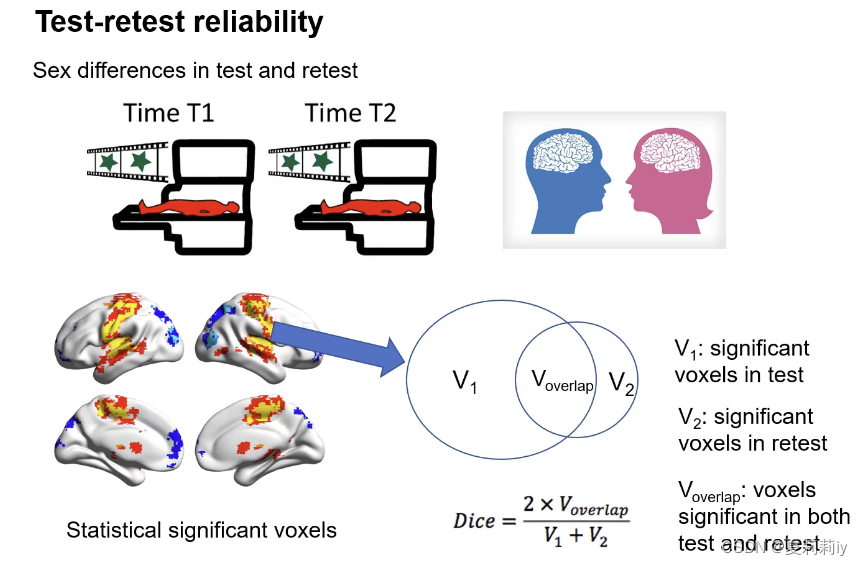

2.4. Test-retest Reliability